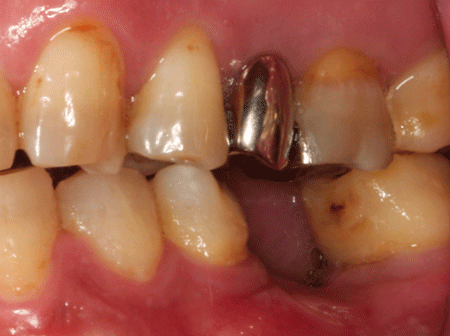

2024.12.1560代男性 痛みのあるブリッジを除去してインプラントブリッジを併用し噛み合わせを改善した症例